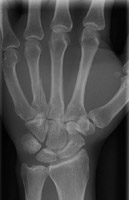

- Click on the image for a larger versionCPA radiograph of the hand. This shows fractures of both the third and fourth metacarpals as well as a Colles fracture.